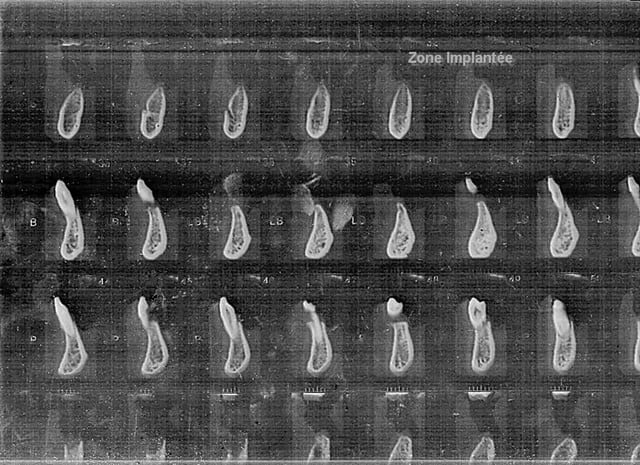

Mon scan de scan est nul. J'essaierai de le prendre en photo. En attendant, voilà:

Je précise qu'il y a aussi un implant en position 35. Les implants 44 et 35 portaient des BP jusqu'à maintenant.

Feyscan2b uhqfyy - Eugenol

en effet...on n'y vois pas grand chose...mais à mon avis une expansion est parfaitement réalisable...il m'est déjà arrivé d'implanter dans des zones beaucoup plus fines que çà...

magnifique cas d'expansion. (bone splitting)

pour les scan tu dois avoir un disque c'est plus simple que les photos.